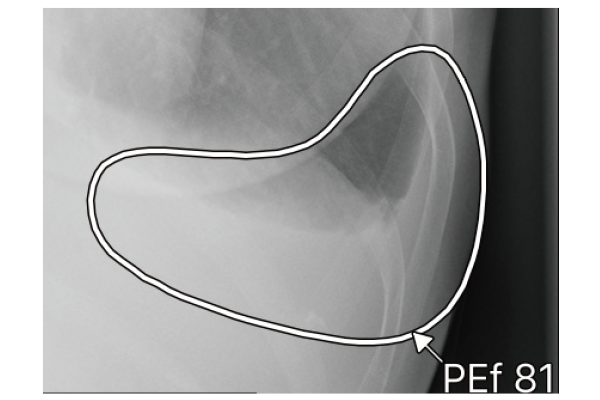

CXR-AIDが候補領域の解析をおこなったのち、0~100に応じた確信度を色分けして表示。

ヒートマップと輪郭の表示は3パターンから選択可能です。